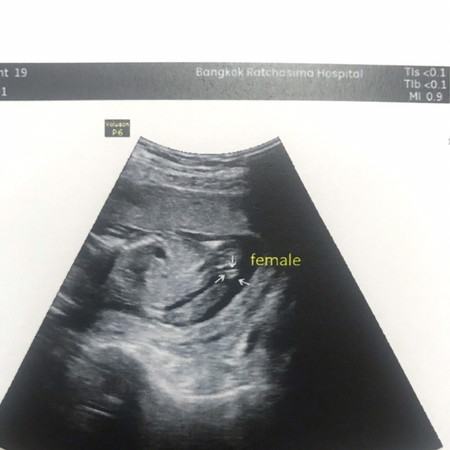

เเบบนี้ผู้หญิง100%ไหมคะ กลัวมีจู๋โผล่ขึ้นมา

เหมือนกันเลยค่ะ กลัวจู๋ชี้🤣🤣 แต่หมอก้อว่าผู้หญิงชัวร์ค่ะ